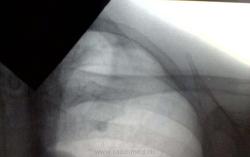

Изменения на верхушке

Пациент 1949 г. рождения. Жалоб не предъявляет. Архив - в порядке. Выявлен на профосмотре. Какие будут мнения?

Т.е. этой тени на 1 ребре не было?. В 1 м/р слева очаг, апикальные плевральные наслоения. Пусть пока будет очаговый твс.

Смотрится как кальцинат, странно что в архиве не было, я бы отпустила

Тоже хотела отпустить, но тормознуло то , что раньше верхушка была чистая.

А сребром это не связано? В смысле хрящ обызвествеленный.

С тем, что хрящ обызвествлён, согласна. Возраст подходящий. Пора. Но основная проблема - на верхушке.

Опухоль Пенкоста?

может очаговый туберкулез?

В итоге отправила пациента к фтизиатру с заключением - очаговый Твс в/доли левого лёгкого.А завершил он свой путь вОД, где прооперирован по поводу периферического С-r в/доли левого лёгкого. Так что, коллеги, будьте бдительны!!!

Рак на самой верхушке, а округлая тень - обызвествление ребра?

Вот эта самая тень оказалась раком? Я бы никогда не подумала

Подробностей пока не знаю. Считаю, что раковые изменения = красная стрелка, а зелёная стрелка= обызвествление рёрерного хряща...

Случай был бы полезным, если бы врачи видели линейные томограммы верхушек лёгких. Предполагаю, что окологи не могли оперировать без данных КТ-исследования. Вы призываете "коллеги, будьте бдительны!!!". Но мы не имеем рентгеновских признаков этой бдительности для использования их в практике. Возраст пациента (65 лет) итак нацеливал врачей на злокачественную патологию. Об этой настороженности написала tarja #12. Но , что её подвигло на этот диагноз — вопрос? Надеюсь tarja напишет. Жду томограммы.

Коллеги, думаю о коварных верхушках никогда не лишне поговорить и показать находки. Правда, показалось что основная тень  по зеленой стрелке (образование, инфильтрат), а розовая -возможный очаг отсева, поскольку томо не были представлены. Считаю, что на верхушки особо пристальное внимание надо обращать, они чреваты сюрпризами. И в данном случае, мне кажется, суть не в том, ЧТО там, а что ТАМ что-то есть и требуется дообследование. Потому спасибо автору за представленный случай.

В левом легком в его верхушке отмечаются локальные очажки затемнения. По началу подумал о туберкулезе, но потом  стало казаться, что в средних отделах 1 ребра имеется участок деструкции костной ткани (опухоль Панкоста)? В проекции переднего отрезка 1 ребра слева обызвествление реберного хряща.